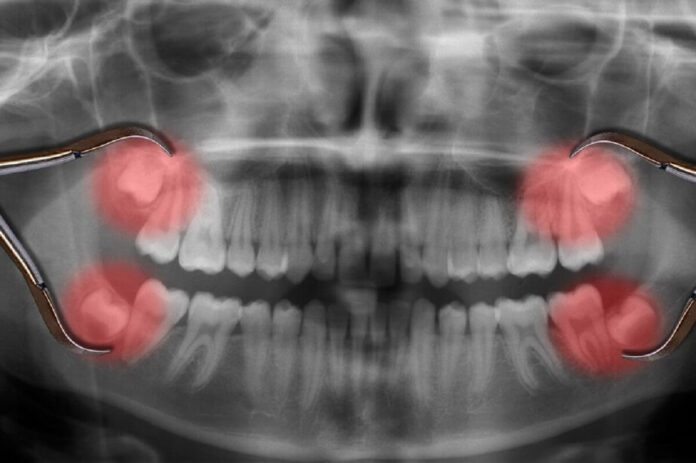

Some people wait until the teeth cause pressure, but early checks keep things simple. Imaging shows how the teeth sit and how much room they need. That gives the dentist a clear way to explain what comes next. A well-timed removal supports comfort and protects nearby teeth.